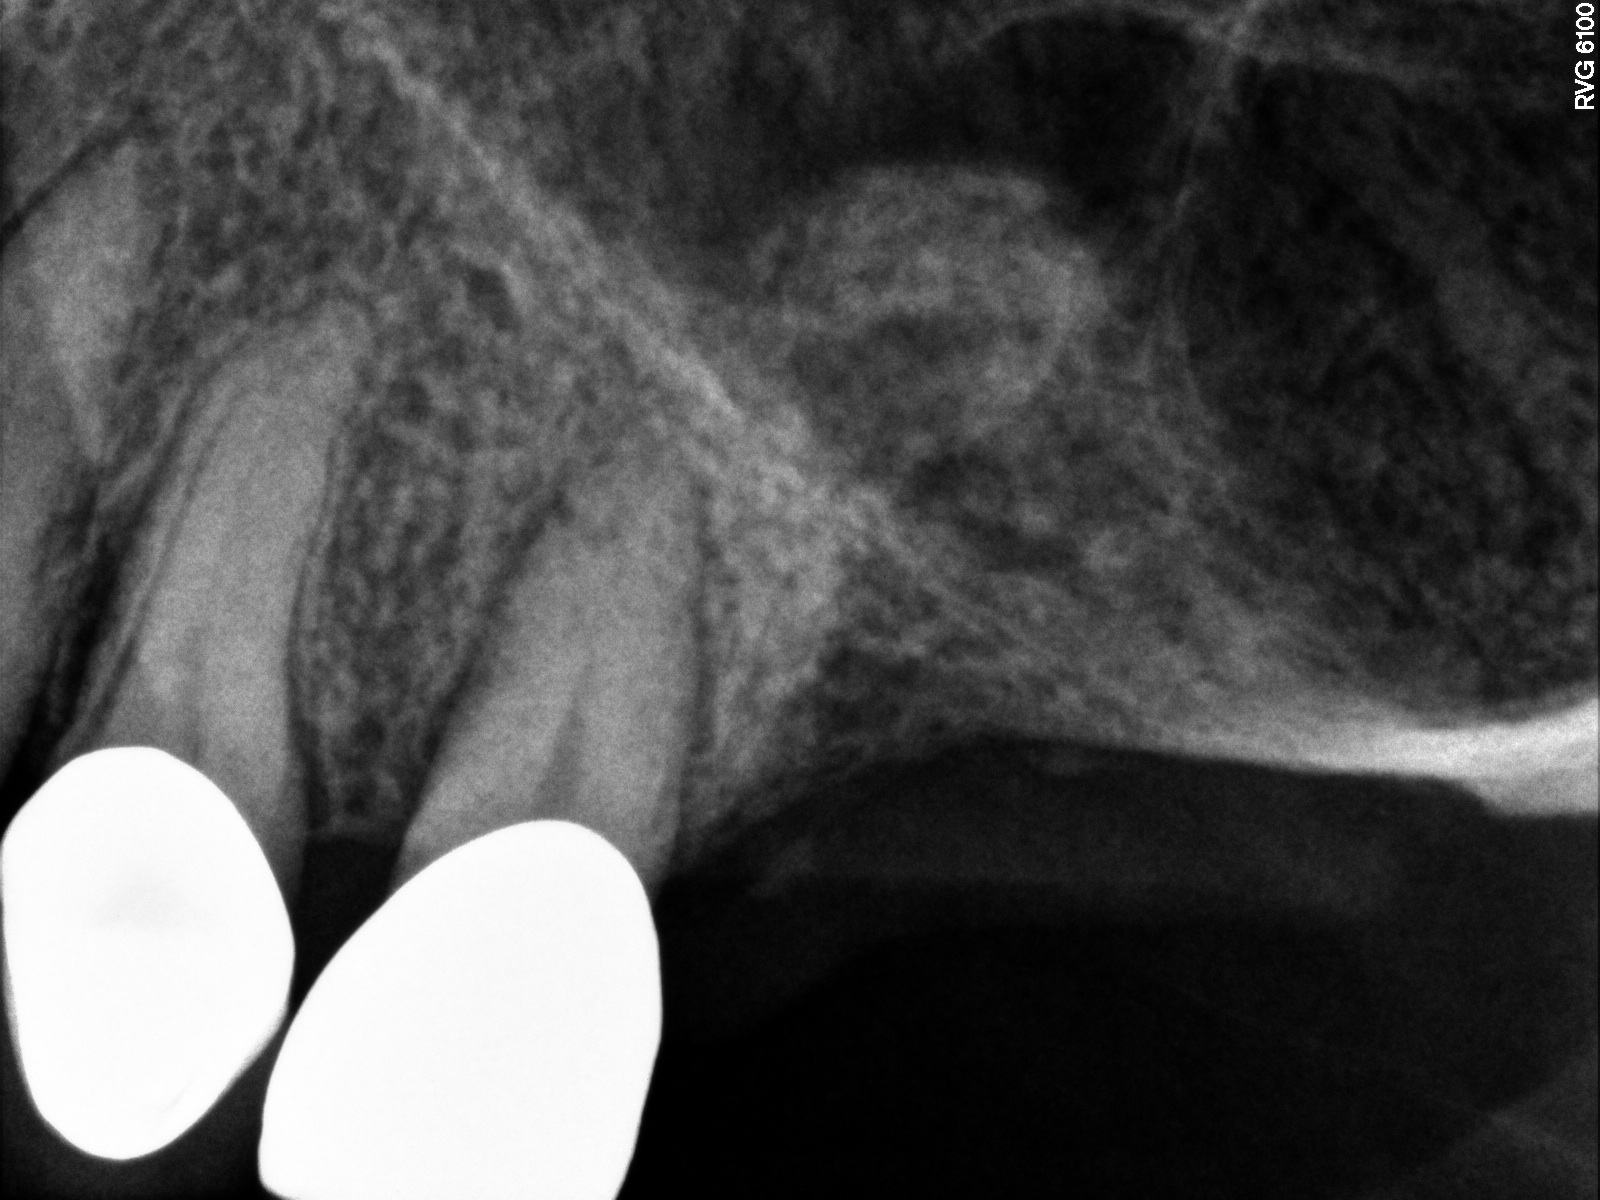

Case 3. Preoperative radiograph showing about 3.5 mm of ridge height.

Fig. 20